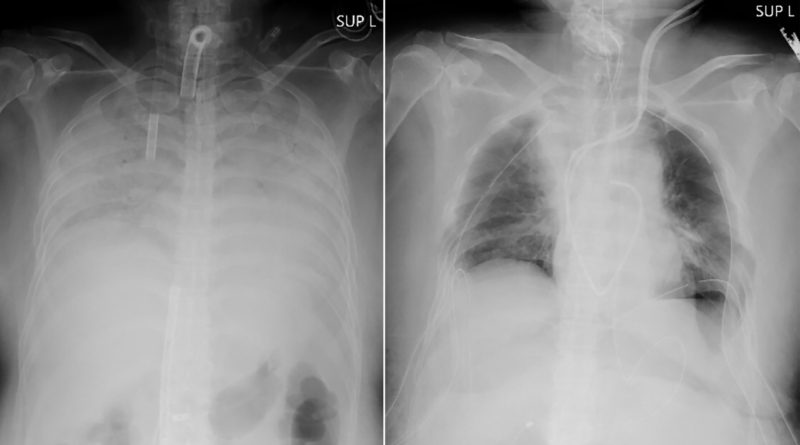

This combination of radiographs provided on April 9, 2021, by Kyoto University Hospital, shows the chest of a patient before the surgery, left, and after the surgery, right. Doctors in Kyoto University Hospital announced Thursday, April 8, 2021, they have successfully performed the world’s first transplant of lung tissue from living donors to a patient with severe lung damage from COVID-19. (Kyoto University Hospital via AP)